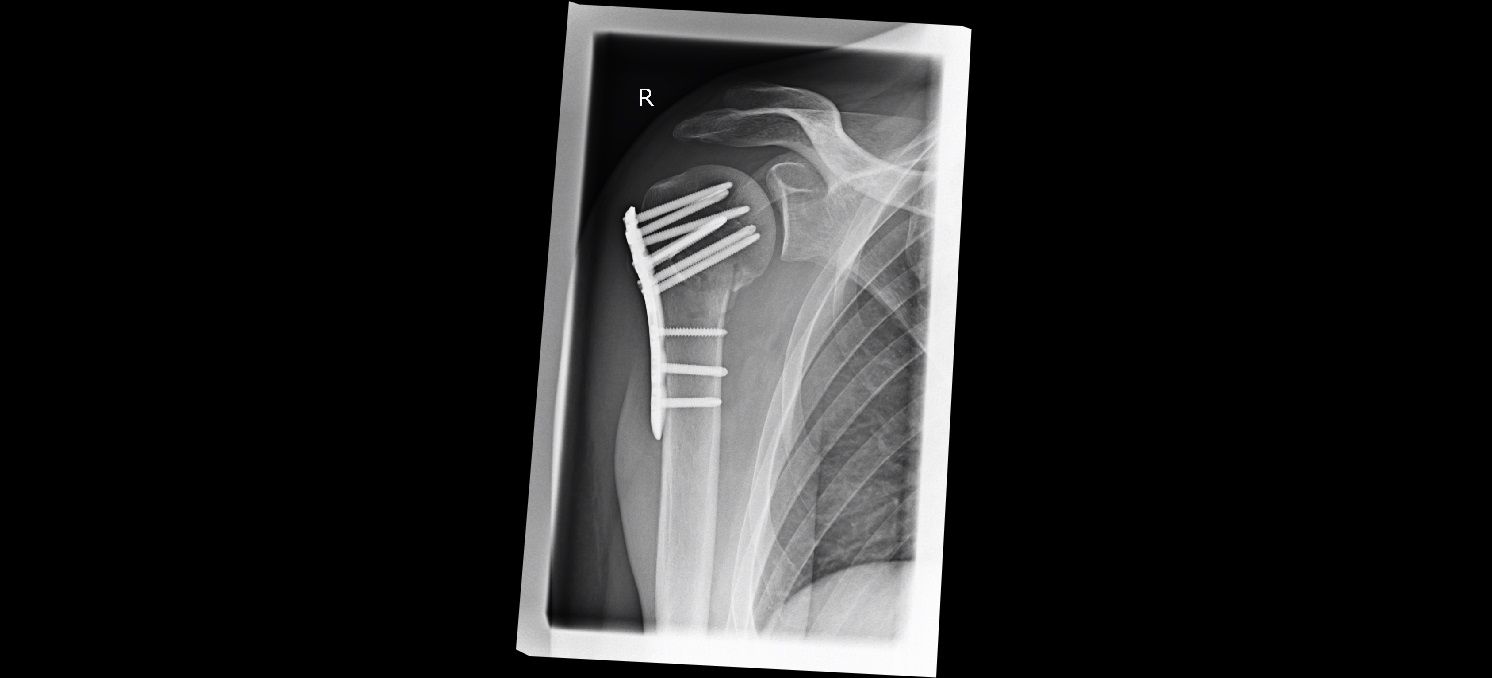

versus die neue Aufnahme:

Anhang anzeigen 952919

Auf der ersten Aufnahme (Seite 3) stand bei 1. etwas vom Knochen ab, was bei der neuen Aufnahme jetzt wieder am Knochen dran ist. Bei 2. war auf dem ersten Bild ein dunkler Streifen zu sehen, der bei der neuen Aufnahme nicht mehr zu sehen ist. Allerdings ist das ganze schwer zu vergleichen, auf der älteren Aufnahme sieht man die Stabilisierungsplatte etwas schräg seitlich, auf der zweiten Aufnahme genau von der Seite.